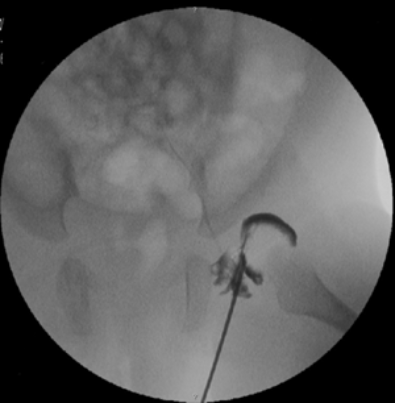

The x-ray shows a hip arthrography

performed by Dr. Zenios.